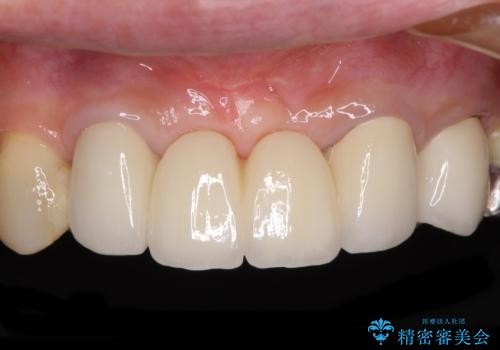

強化セラミッククラウンは単一素材のため、非常に高強度でありますが色調は単調なものとなり、隣在歯と調和させることは困難です。